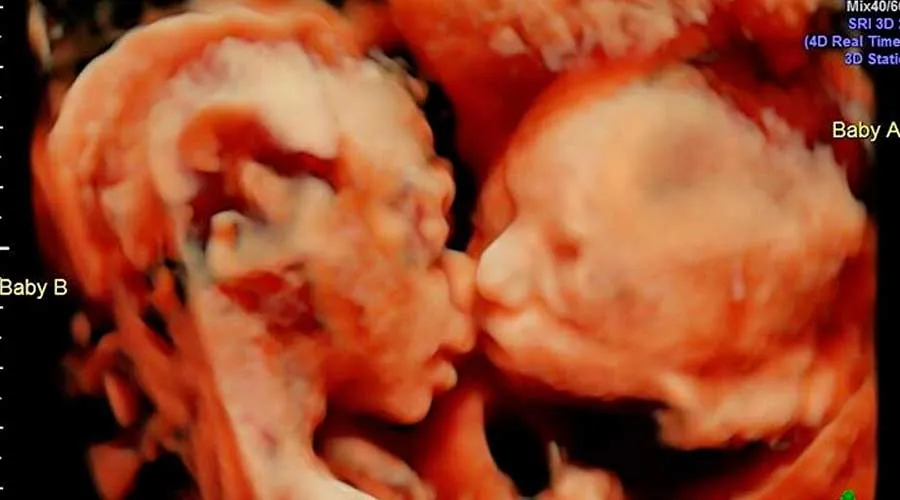

FOTO VIRAL: Ultrassom capta gêmeas dando terno beijo no ventre materno

Uma mulher norte-americana com 25 semanas de gravidez descobriu algo curioso quando fez uma ultrassonografia: viu suas gêmeas dando um... Leia mais